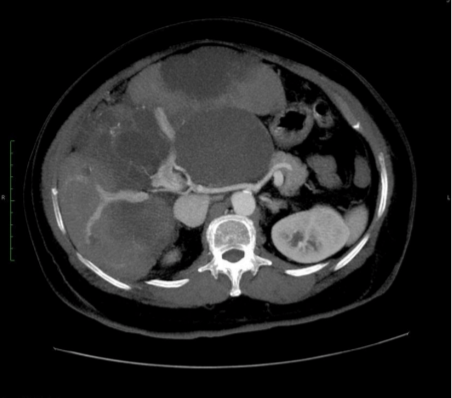

A tomografia computadorizada de abdômen, conhecida também como TC abdominal, é um exame de imagem de alta qualidade e de grande importância no diagnóstico de doenças do fígado, pâncreas, rins, baço, intestino, glândulas suprarrenais, cólon e outros.

A tomografia abdominal tem inúmeras indicações, como lesões no abdômen, suspeita de tumores, de apendicite, pedras nos rins, diverticulite ou mesmo de infecção ou inflamação abdominal. Quando a suspeita é de um trauma no abdômen, os médicos buscam por líquidos ou hemorragias dentro ou fora dos órgãos.